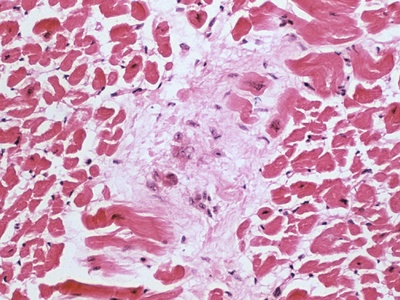

Myocarditis

Inflammation of heart muscle that can reduce pumping function and cause arrhythmias. Triggers include viral infections and immune responses. Symptoms range from mild to life-threatening; seek care for chest pain, breathlessness, or syncope.